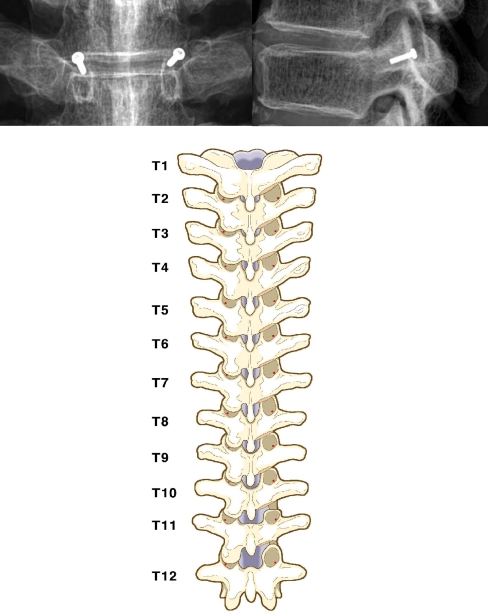

A posterior midline incision was made and subperiosteal dissection carried out. Periarticular soft tissue was cleared to expose the facet joint and tips of the transverse process. With a 2-mm osteotome, approximately 5 mm of inferior articular process, which overhangs the base of the superior articular process, was removed so as to expose the base of the superior articular process situated to the right of the medial to lateral border. A vernier caliper with an accuracy of 0.1 mm was used to correctly identify the junction of the lateral one-third and medial two-thirds of the base of the superior articular process. The orientation of the transverse process was not considered throughout the procedure. However, at the end of the procedure the authors observed that this point was always slightly superior to the superior border of the transverse process. A 2-mm circular metal marker was placed over the proposed entry point (Fig. 1). In order that the X-ray beam be parallel to the end plates the radiographs were taken in three parts by centering the beam over the upper, middle and lower thoracic spine, respectively. The pedicle shadow can be easily identified by this method. The superior and lateral distance of the ideal pedicle entry point (IPEP) from the centre of the pedicle was then calculated using Rapidia ver. 2.7 software (INFINITT, Seoul, Korea). The accuracy of the software was 0.1 mm. Using the lateral radiograph, we attempted to find out the ideal sagittal angle for placement of the screw. The points considered were the centre of the metal marker and the junction of the upper one-third and lower two-thirds in the middle of the corresponding body. Two lines were then drawn, one along these two points and the other along the superior border of the body. The angle was then measured using the same software. The accuracy was 1°. To determine the horizontal angle a computed tomography (CT) scan was then performed with 2-mm-thick cuts. The points that were considered were the midpoint of this metal marker and the midpoint of the isthmus. One line was drawn along these points and the other line was drawn to bisect the vertebrae. The angles were measured using the same software with an accuracy of 1°. The whole procedure was carried out on one side by one spine surgeon and on the other side by the other surgeon. The two observations were blinded, and we were able to determine the interobserver reliability in identifying the IPEP.

Fig. 1.

Plain roentgenography shows the superolateral entry point in the anteroposterior view (left), and the superior location of the entry point in the lateral view (right). Posterior view (bottom) of the thoracic spine shows the pedicle screw entry points (red points) following the one-third and two-thirds rule